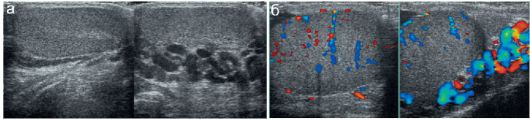

Проба вальсальвы яичек

Проба вальсальвы яичек 117 фотографий